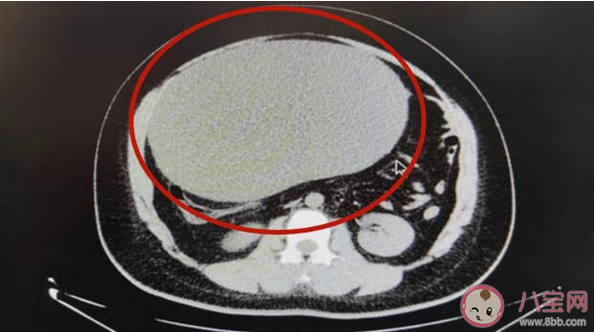

CT檢查后顯示,曉琪腹部有一個巨大的卵巢囊腫,這個囊腫壓迫著周圍的腸管與左側子宮附件,并且這個囊腫已經發(fā)生了扭轉,如果治療不及時很可能導致該側卵巢壞死。

最終,醫(yī)院為她實施了卵巢囊腫剔除術,手術切除下的囊腫重達16斤,比一個足球都大。